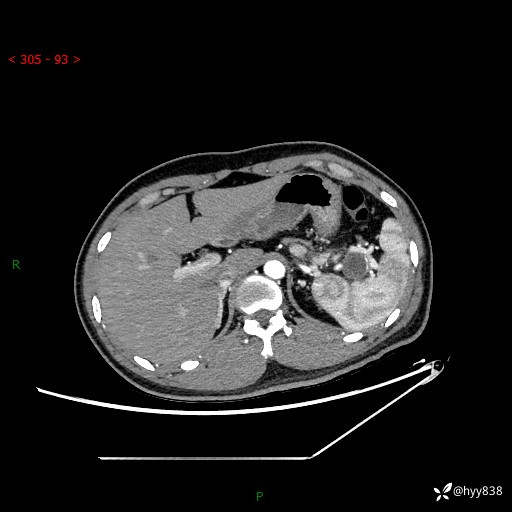

【患者信息】:31岁/男

【主诉】:间断性左下腹疼痛10天

【现病史及既往史】: 患者10余天前无明显诱因出现左下腹部疼痛,呈间断性,无恶心,呕吐,无黄疸,腹泻症状,于当地医院就诊,行腹部C提示:胰腺尾部占位。2型糖尿病。现患者为求手术治疗,门诊以“胰腺肿物”收入院。 患者起病来,一般情况可,大小便正常,体重体力未见明显减轻。

【检查】:胰腺CT平扫+增强